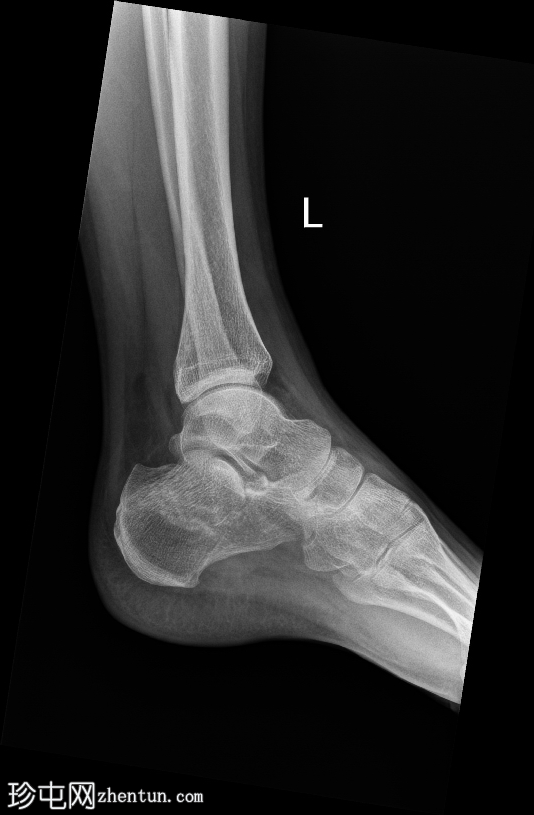

斜位片

左侧跟骨关节内粉碎性骨折。骨折线贯穿跟骨体,累及并破坏距下关节后关节面,并沿跟骨外侧可见一处骨折。骨折始于距下关节中央,向下向后延伸。跟骨整体高度降低,后关节面凹陷,Böhler角变平,Böhler角明显减小,提示后关节面凹陷。

距骨、舟骨以及外踝和后踝均完整,踝穴和韧带联合完整。距下关节和跟骰关节未见脱位。软组织肿胀亦可见。

跟骨骨折是跗骨中最常见的损伤,通常由轴向负荷力引起,例如高处坠落或高强度冲击创伤。本例左侧跟骨的侧位片和轴向片显示,关节内粉碎性骨折延伸至距下关节后关节面,伴有高度降低和后关节面凹陷。

Sanders 分类根据跟骨后关节面的 CT 表现对关节内骨折进行分类,根据该分类,该损伤很可能属于 II 型或 III 型骨折。这些类型涉及一条或多条穿过后关节面的骨折线,并伴有不同程度的粉碎和移位。